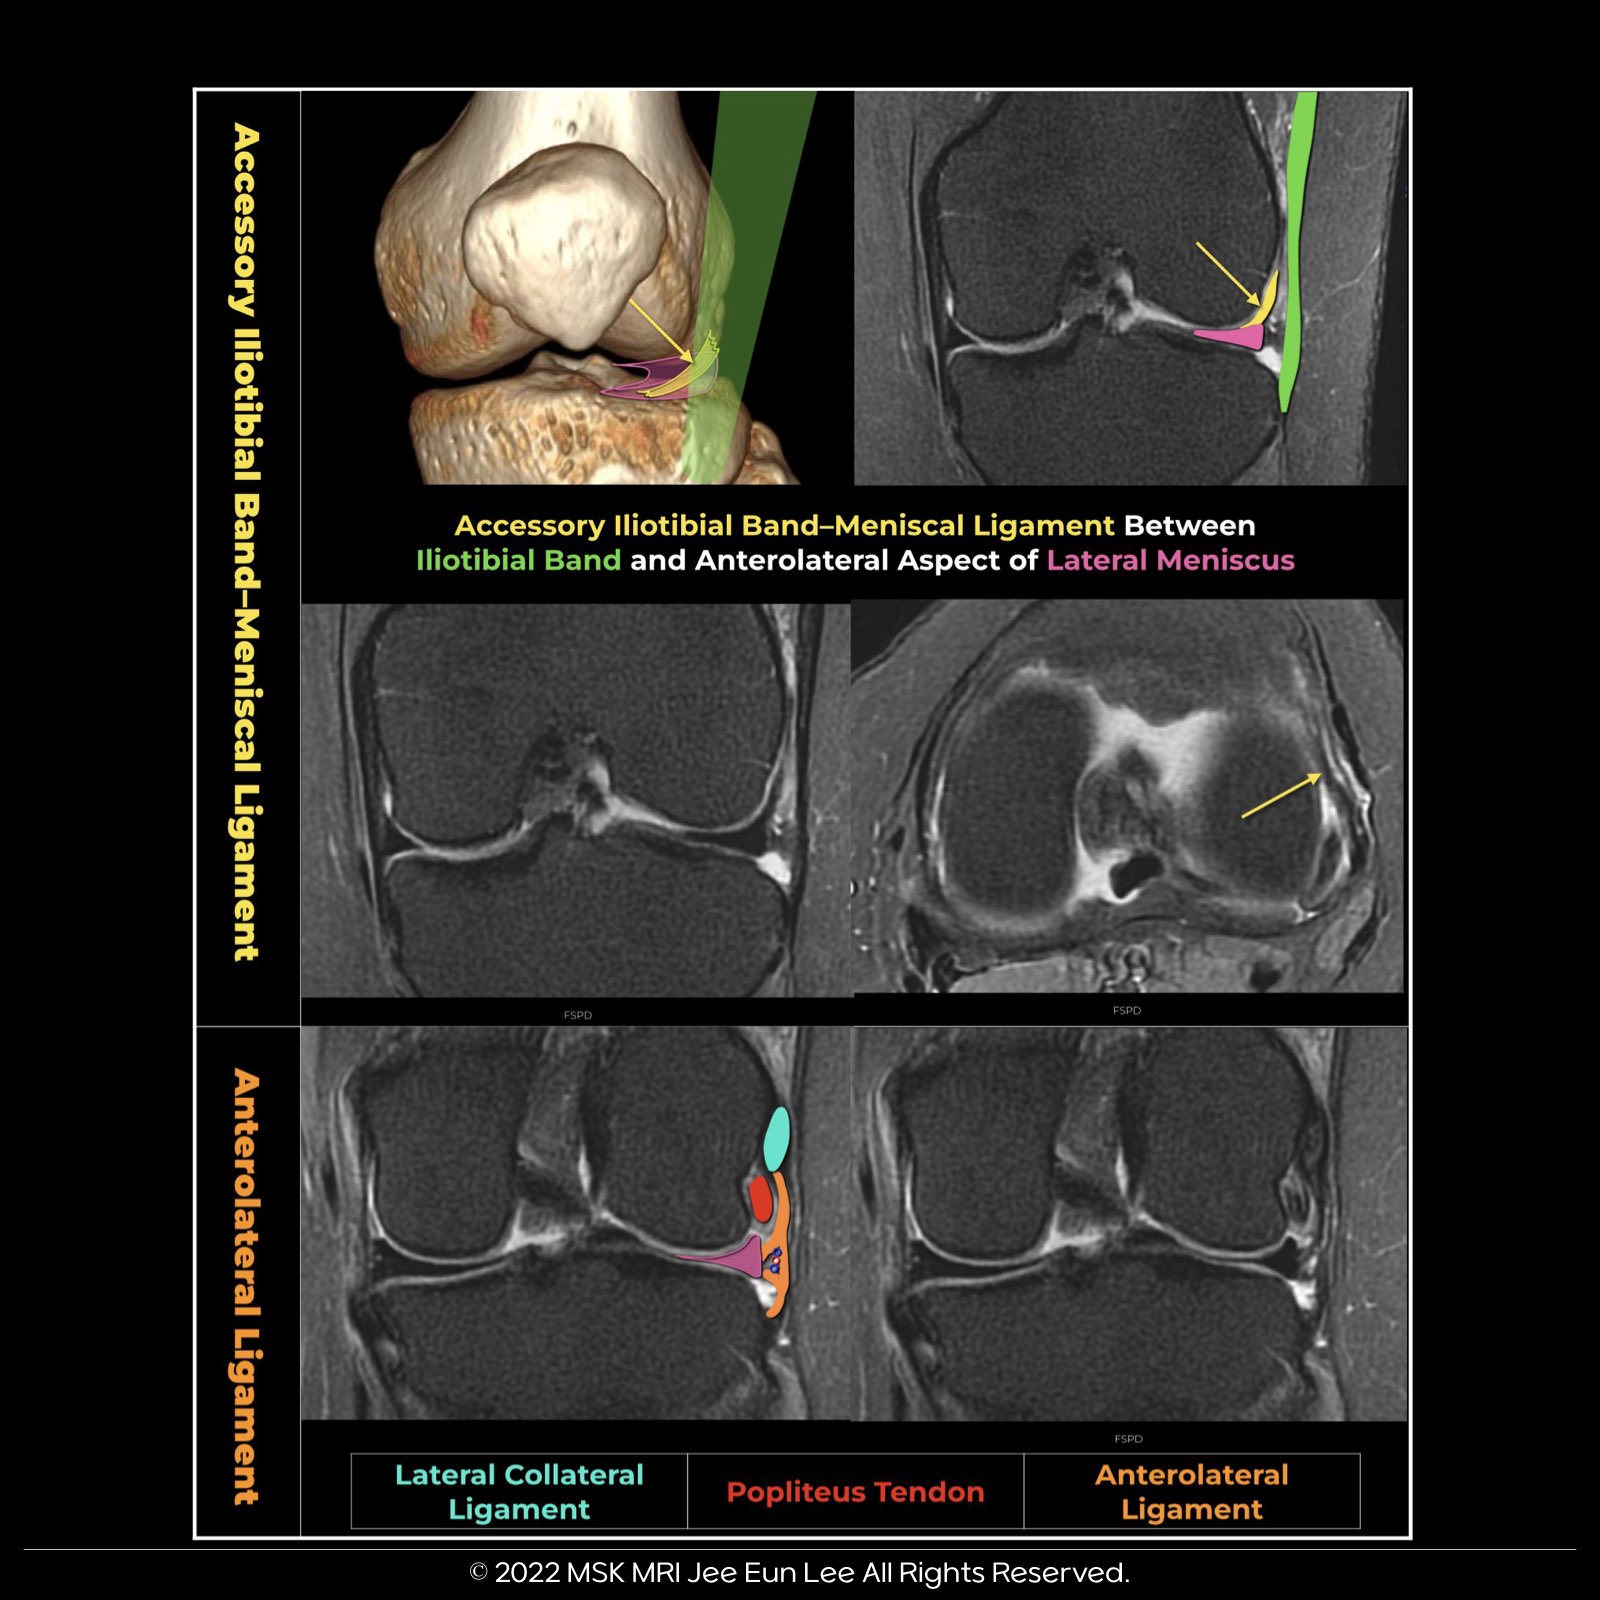

Accessory Iliotibial Band–Meniscal Ligament (AIML)

The anatomic variation of the anterolateral fixation of the lateral meniscus to the ITB, which we have termed the “accessory iliotibial band–meniscal ligament” or “AIML.”

An AIML was present in 13.3% of all patients (136/1019).

The presence of an AIML is strongly associated with:

- Tears of the anterior horn and body of the lateral meniscus

- Intrasubstance abnormalities

- Parameniscal cysts

- Hoffa edema